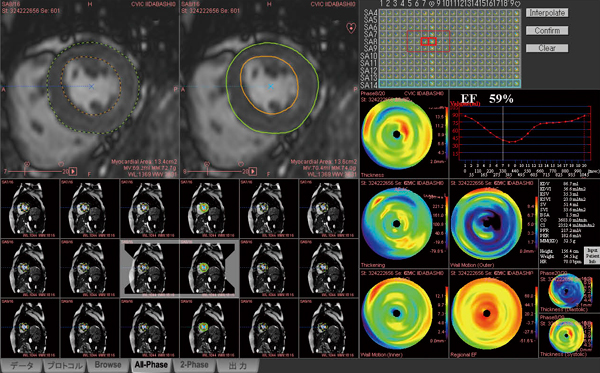

図5 症例2:ZIOSTATIONによる 左室壁運動解析

冠動脈スクリーニング症例にも,必ずシネMR画像を用いて左室壁運動解析を施行している。EF(左室駆出率)のほか,EDF(左室拡張末期容積),ESV(左室収縮末期容積),SV(1回拍出量),CO(心拍出量),CI(心係数)を表示し,正常値との差を明確にしている。また,心位相と左心室内腔容積の関係を示す時間容積曲線とPFR(Peak Filing Rate),PER(Peak Ejection Rate)を算出して,左心室の拡張能や収縮能も評価している。